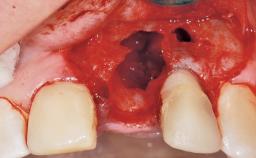

Late Placement of an Implant in a Maxillary Left Central Incisor Site

A 30-year-old female patient had lost tooth 21 and was referred to our clinic for consultation and treatment. Due to advanced apical infection, tooth 21 had been extracted two months earlier at another clinic and an acrylic-resin tooth had been bonded to the adjacent teeth. The patient desired implant treatment to avoid any damage to the adjacent natural teeth. While the patient had no history of any systemic disorder, she was a heavy smoker and exhibited medium to advanced periodontitis in the entire jaw. After the initial treatment to achieve a pocket probing depth of less than 4 mm and no bleeding on probing, a decrease in the height of the papillae mesial and distal to the extraction site and overall gingival recession were observed.

Bone Augmentation Horizontal|Staged

Augmentation Materials Autogenous chips|Membrane

Bone Volume Deficient horizontally, requiring prior grafting